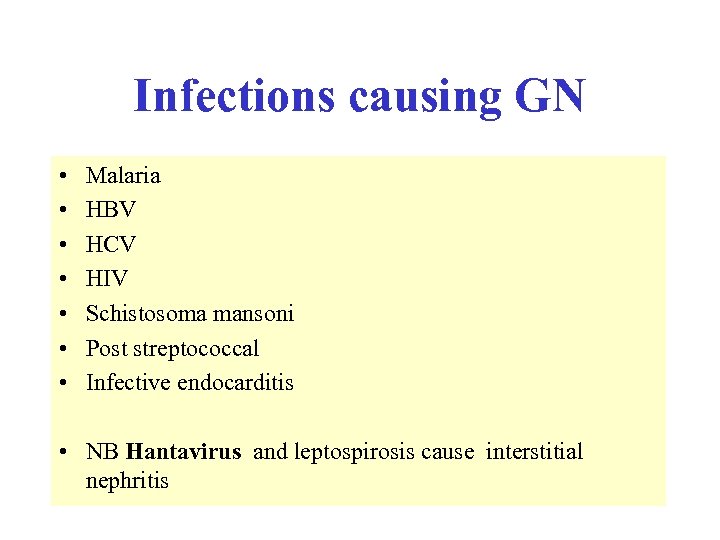

Reduced serum complement • • Occurs in: - SLE - infective endocarditis - post strep nephritis - shunt nephritis - cholesterol embolism - cryoglobulinaemia - MCGN types 1 and 2 • • Complement normal in FSGS, amyloidosis, Alports, anti GBM disease C 3 nephritic factor is an Ig. G auto antibody to the C 3 convertase of the alternative pathway of complement activation, found in both types of MCGN